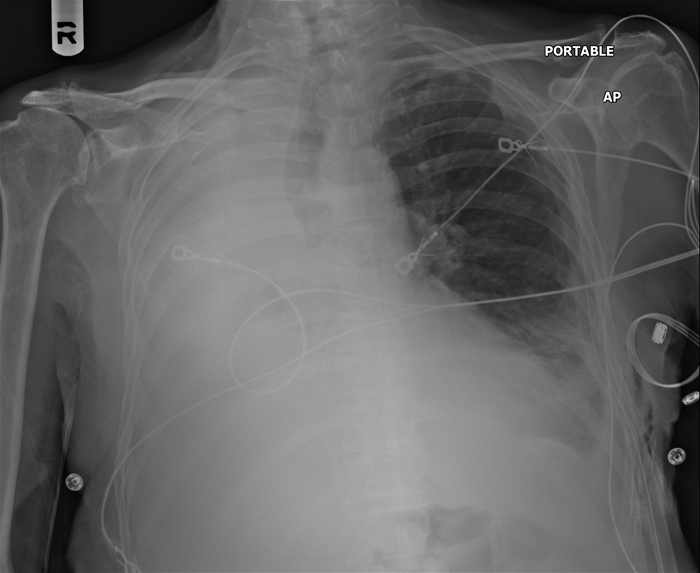

A 65-year-old man with a long history of smoking comes to the emergency department with shortness of breath and a chronic mild cough.  His symptoms progressed gradually over the last week and today have become suddenly worse.  The patient has hypertension that is controlled with hydrochlorothiazide.  On examination, his temperature is 36.7 C (98 F) , blood pressure is 135/85 mm Hg, pulse is 94/min, and respirations are 24/min.  Pulse oximetry shows 86% on room air.  He has decreased breath sounds over the right chest.  His chest x-ray is shown in the image below. A 65-year-old man with a long history of smoking comes to the emergency department with shortness of breath and a chronic mild cough.  His symptoms progressed gradually over the last week and today have become suddenly worse.  The patient has hypertension that is controlled with hydrochlorothiazide.  On examination, his temperature is 36.7 C (98 F) , blood pressure is 135/85 mm Hg, pulse is 94/min, and respirations are 24/min.  Pulse oximetry shows 86% on room air.  He has decreased breath sounds over the right chest.  His chest x-ray is shown in the image below.   Which of the following is the most likely cause of this patient's radiographic findings? A) Fluid in the alveolar spaces B) Interstitial lung disease C) Pleural space disease D) Pulmonary vascular disease E) Right mainstem bronchus obstruction Which of the following is the most likely cause of this patient's radiographic findings?